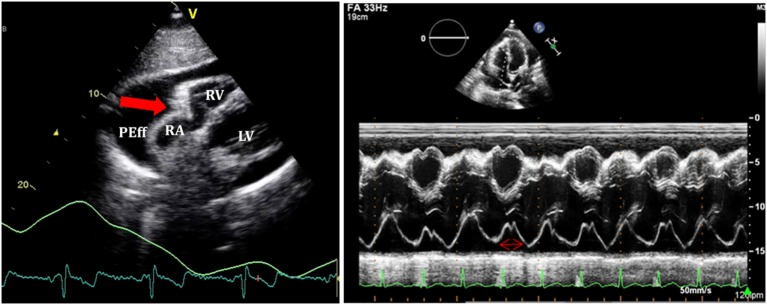

The image above demonstrates a small to moderate-sized circumferential pericardial effusion.  The effusion is seen by the anterior anechoic strip between the epi and pericardium. Effusions typically collect posteriorly/inferiorly, but will become circumferential as they get larger. Effusions around the anterior aspect of the heart may be differentiated from epicardial fat by their anechoic nature, whereas fat substance may be punctuated with mixed echogenicity. (1)

Right atrial collapse: While brief collapse of the RA wall during systole can be a normal variant, collapse lasting more than 1/3 of systole is almost 100% sensitive and specific for tamponade.  This phenomenon is best observed and measured using M mode (Figure 1), but may be difficult to discern in a tachycardic patient. (1)

Figure 1: On left, visualization of right atrial collapse.  On right, M mode allows temporal  measurement of collapse. (2)